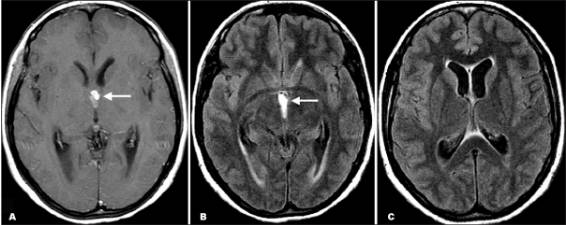

Hình ảnh trên phim chụp cộng hưởng từ cũng là công cụ hữu ích để chẩn đoán ATSL thể thần kinh và có thể tốt hơn cả chụp cắt lớp CT để phát hiện các thương tổn trong não tủy, trong cuống não, trong não thất. Việc áp dụng nó nên cân nhắc khi CT-scanner không chẩn đoán ra. CT và siêu âm là rất nhạy để phát hiện các tổn thương ATSL tại mắt và hệ cơ xương.